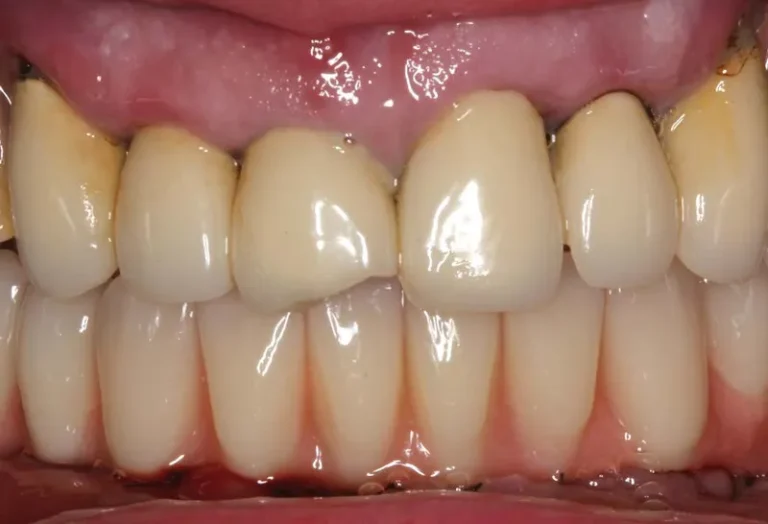

Mantener unas encías saludables es fundamental cuando tienes implantes dentales, ya que la longevidad y el éxito de estos dependen directamente de la salud del tejido gingival que los rodea. La higiene adecuada, el uso de herramientas específicas como cepillos interdentales y una técnica correcta de limpieza son esenciales para prevenir la periimplantitis y otras…

Los implantes dentales y los dientes naturales presentan características únicas que los diferencian tanto en estructura como en funcionamiento. Mientras los dientes naturales cuentan con ligamentos periodontales que proporcionan sensibilidad y capacidad de adaptación, los implantes se integran directamente al hueso mediante oseointegración. Esta distinción fundamental influye en aspectos como la sensibilidad a la temperatura,…